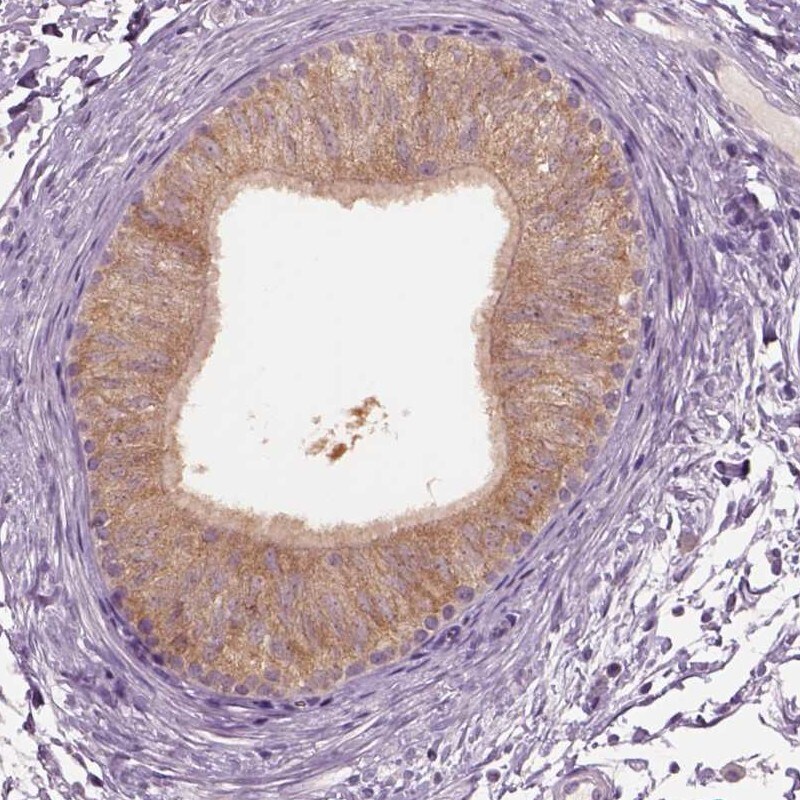

Supportive validation

- Submitted by

- Invitrogen Antibodies (provider)

- Main image

- Experimental details

- Immunohistochemical staining of CLPSL1 in human epididymis using CLPSL1 Polyclonal Antibody (Product # PA5-67272) shows high expression.